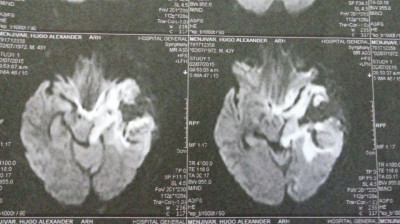

Imagen Post Operatorias 3 días después

Imagen Post Operatorias 3 días despues